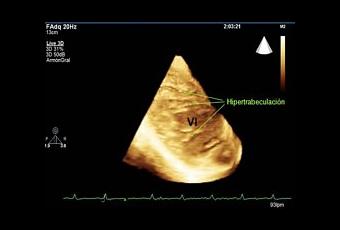

La hiper-trabeculación de ventrículo izquierdo (HACVI) es una característica típica de ciertos tipos de miocardiopatía (enfermedad crónica del músculo del corazón). La anormalidad es la causa principal de muerte súbita cardíaca relacionada con el ejercicio en atletas.

Los investigadores observaron a 692 atletas en el Reino Unido y encontraron que casi el 7 por ciento de ellos tenía la anomalía, en comparación con el 0,4 por ciento de los no atletas. Y la condición se halló mucho más común en los atletas masculinos negros (13 por ciento) que en los otros atletas (4 por ciento).

La alta prevalencia de HACVI entre los atletas sugiere que esto puede representar una parte del espectro de las adaptaciones cardíacas que se sabe que constituyen “corazón de atleta”. El entrenamiento deportivo regular conduce a cambios en el funcionamiento y la estructura del corazón.

Teniendo en cuenta que HACVI es una característica de la muerte súbita cardíaca, su prevalencia entre los atletas crea mayores retos para los médicos que tratan de diferenciar entre el corazón de atleta y una condición médica seria, sobre todo en los atletas masculinos negros, donde la prevalencia es mucho mayor.